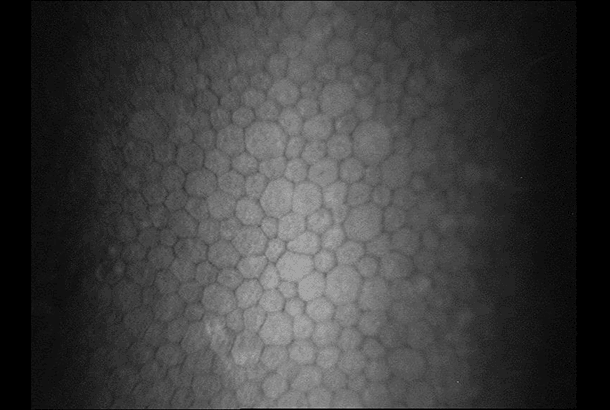

"name": "Polymegethism",

"detail": "<h2>Symptoms</h2>\n\n<ul>\n\t<li>None</li>\n</ul>\n\n<h2>Signs</h2>\n\n<ul>\n\t<li>Variation in cell size and cell shape (pleomorphism) of the endothelium; seen with high magnification (40x) in the endothelial specular reflection</li>\n</ul>\n\n<h2>Etiology</h2>\n\n<ul>\n\t<li>Thought to result from chronic hypoxia causing corneal acidosis following wear of lens with a low Dk/t</li>\n\t<li>Common in long-term wearers, especially of PMMA and low Dk/t hydrogel lenses</li>\n</ul>\n\n<h2>Prevalence</h2>\n\n<ul>\n\t<li>Rare with modern materials</li>\n</ul>\n\n<h2>Differential Diagnosis</h2>\n\n<ul>\n\t<li>Other&nbsp;<a href=\"/condition/62\">endothelial anomalies</a>&nbsp;and corneal dystrophies</li>\n\t<li>See: <a href=\"/condition/62\">Endothelial Changes &ndash; Differential Diagnosis</a></li>\n\t<li><a href=\"/condition/61\">Corneal Exhaustion Syndrome</a></li>\n</ul>\n\n<h2>Management</h2>\n\n<ul>\n\t<li>Refit with a lens of high Dk/t (SiHy), or change to DW / reduce wearing time</li>\n</ul>",